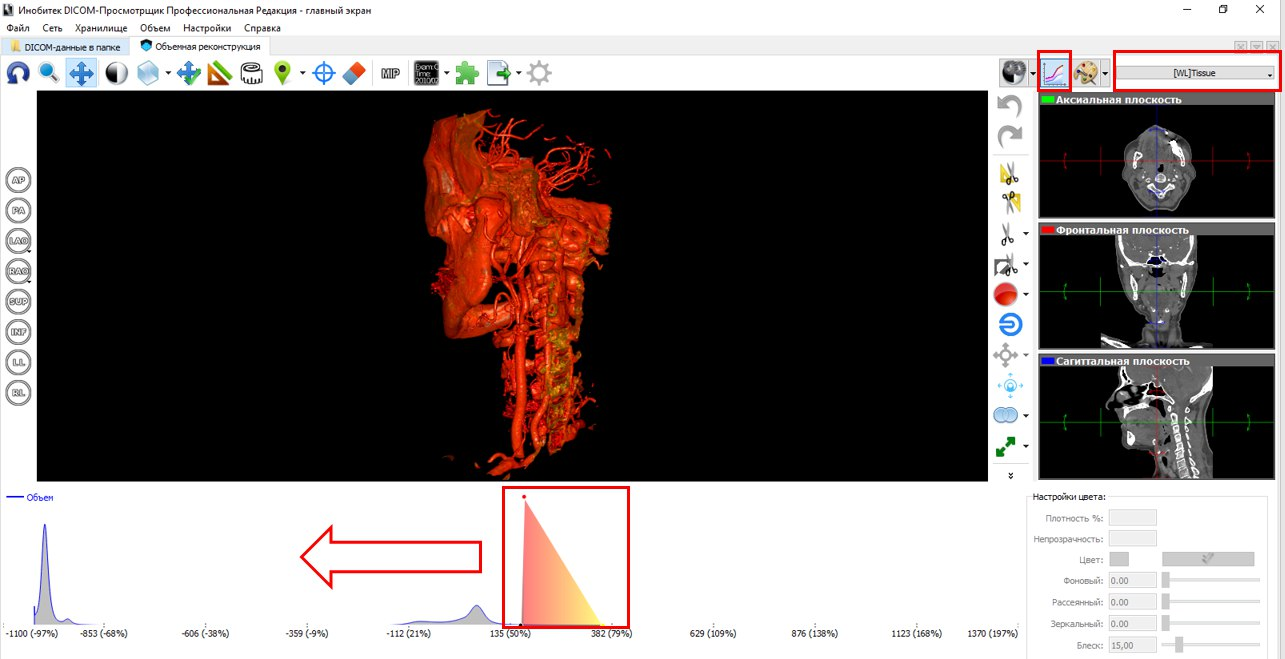

Лазерная камера сетевая для печати изображений на пленке стандарт dicom